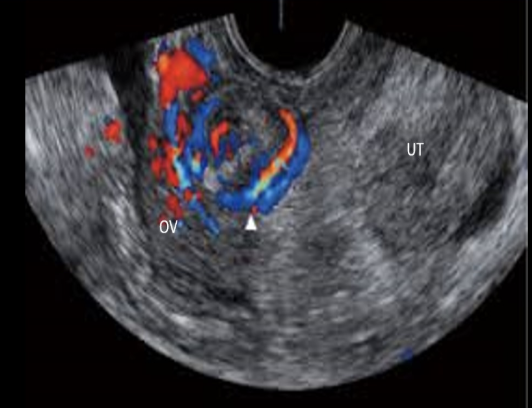

pt has amenorrhea + hirsutism. if the right ovary has the same appearance,

a) normal ovary w/multiple follicles

b) partial ovarian torsion

c) ovarian hyperstimulation

d) possible stein-leventhal syndrome